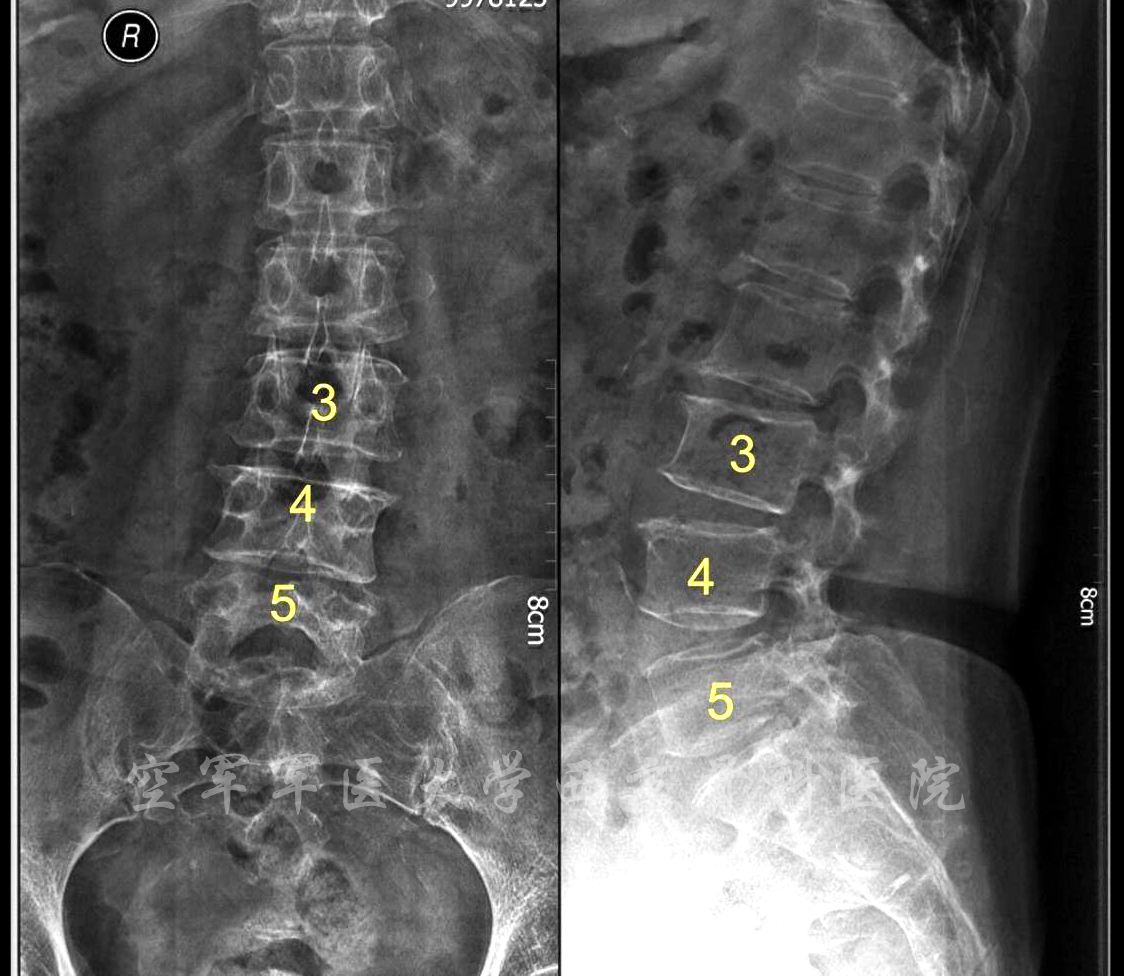

术前X线正侧位片